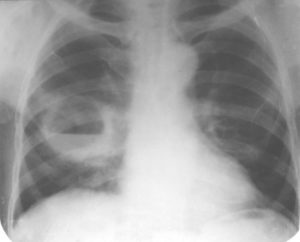

У пациентки затемнение в правом легком, что характерно для долевой пневмонии.

У пациента 76 лет выявлена тень правом легком. Первоначально подозревался периферический рак легкого, но диагноз у данного больного — гамартома правого легкого.